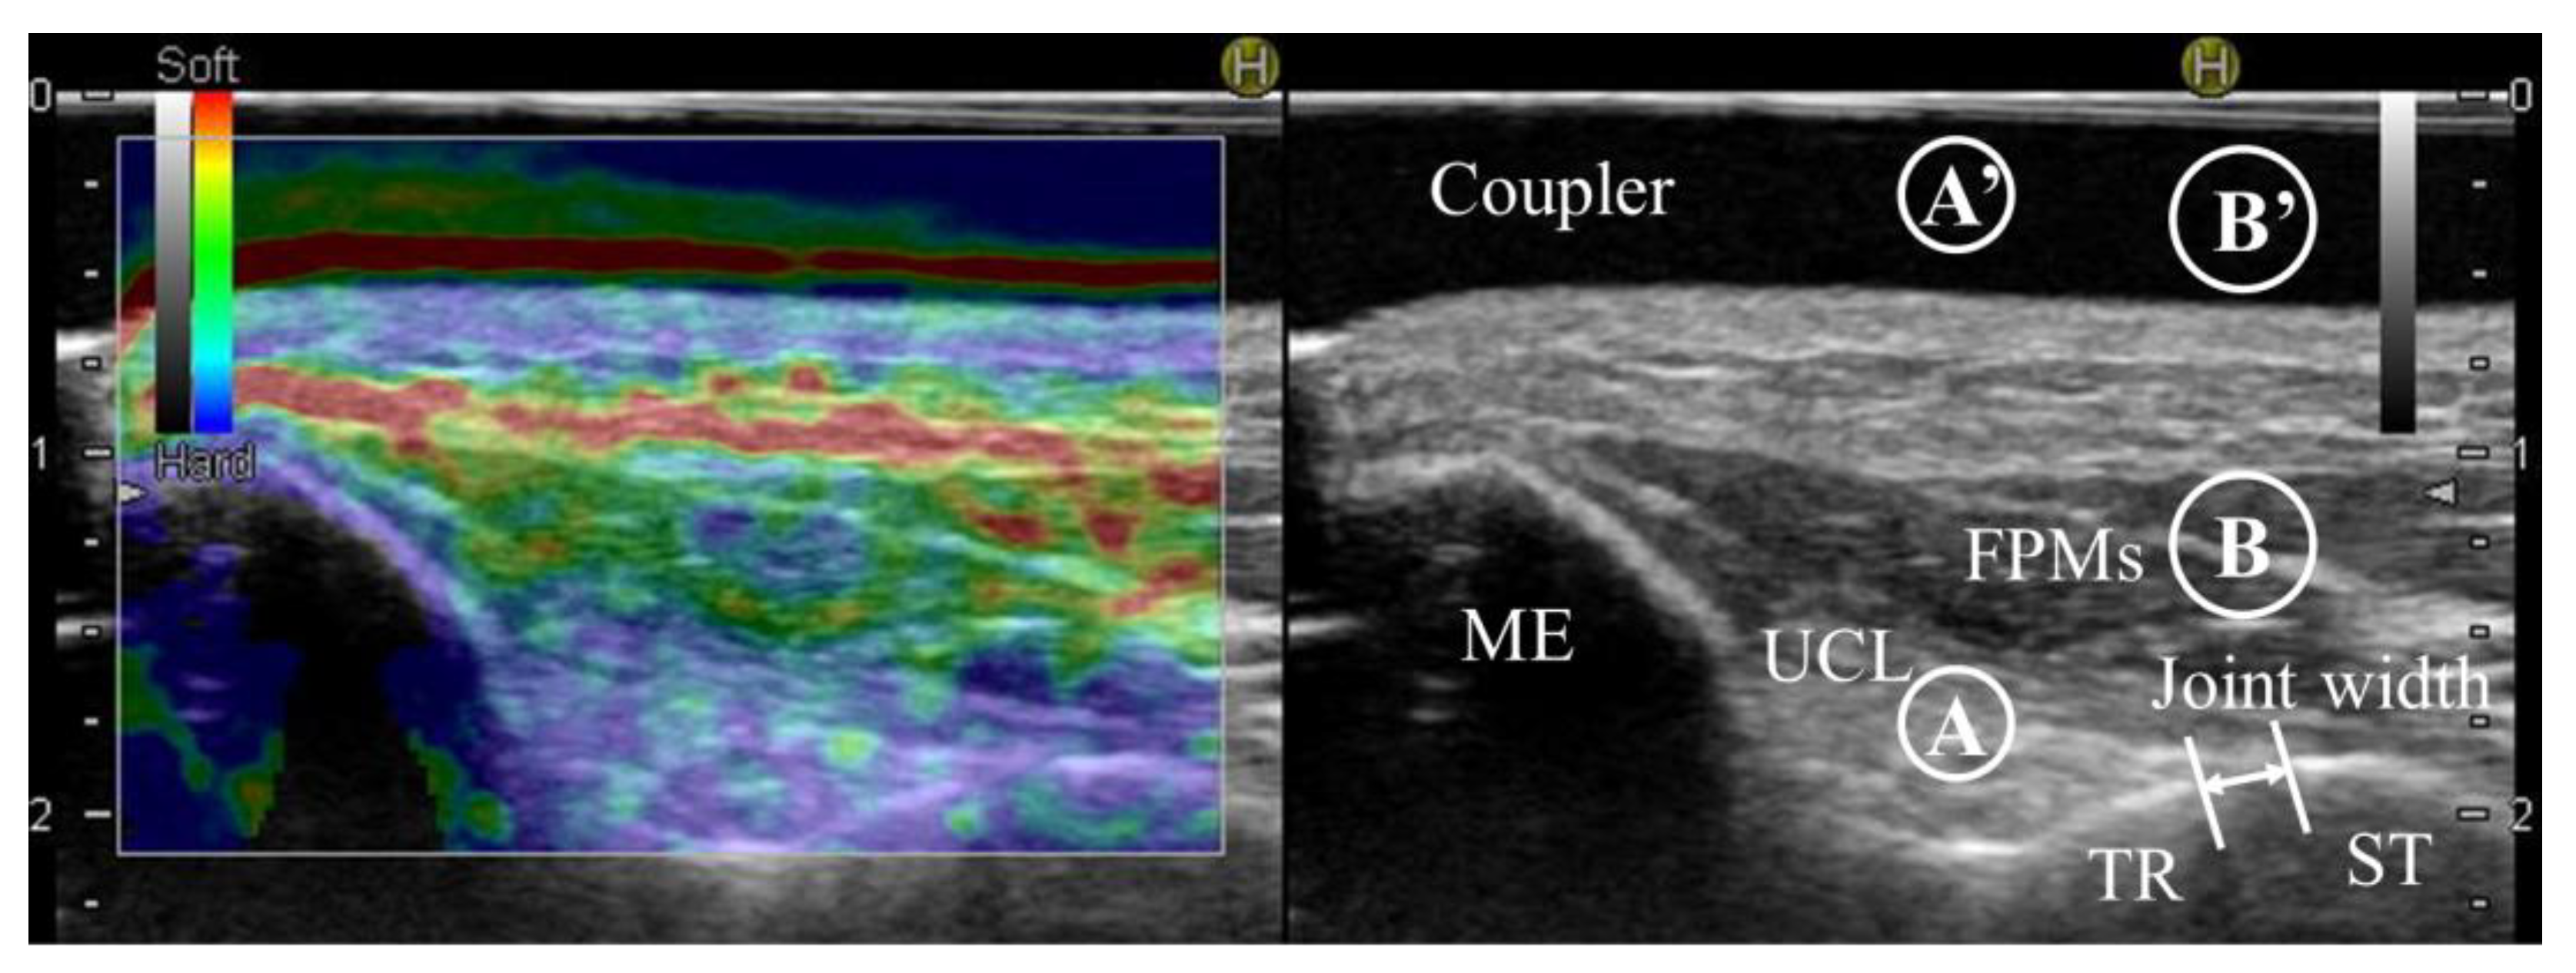

An ultrasound imaging system (Noblus; Hitachi Aloka Medical, Tokyo, Japan) and an ultrasound 18–5 MHz linear array transducer (L64; Hitachi Aloka Medical, Tokyo, Japan) were used to measure the medial elbow joint width in B-mode and the strain ratio indicative of tissue hardness in UCL and FPM in real-time ultrasound sonoelastography (Figure 2). In addition, grip strength was measured for subject characteristics. One experienced physical therapist (H.H.) with over 11 years of experience using ultrasound imaging systems performed all measurements.

Real-time ultrasound sonoelastography colors ultrasound images according to tissue hardness (red, soft; yellow to green, medium; blue, hard) and can measure strain ratio indicative of tissue hardness. Strain ratios indicative of the hardness in the UCL and FPMs were quantified by attaching an acoustic coupler (EZU-TECPL1, Hitachi Aloka Medical, Tokyo, Japan) to the transducer and using the coupler region (just above the target region) as the reference region. Greater strain ratio values indicate harder tissues (stiffer tissues), while less values indicate softer tissues. The UCL measurement region was defined as a circle with the maximum ligament width at the midpoint. The FPMs measurement region was defined as a circle 0.5 cm in diameter at the superficial layer of the FPMs above the ulnohumeral joint. Selection of the measurement region was performed on the B-mode image so that the examiner would not be influenced by the coloring of hardness on the image. The examiner performed the process from image extraction to measurement three times. The average of the three trials was then used for data analysis. The reliability of these assessment methods has been reported as good to excellent (ICC1,3: UCL, 0.91 and 0.83; FPMs, 0.85 and 0.80) [22]. In addition, the ratio of strain ratio UCL/FPMs was calculated from the measured UCL and FPMs data to evaluate the hardness of FPM relative to UCL. A smaller value in the ratio of strain ratio UCL/FPMs indicates the harder tissue of FPMs relative to that of UCL.

Figure 2. Evaluation of ultrasound images. The elastography image on the left is colored for each tissue hardness (red, soft; yellow to green, medium; blue, hard). The image on the right is a B-mode image. ME, medial epicondyle of humerus; TR, trochlea of humerus; ST, sublime tubercle of ulna; UCL, ulnar collateral ligament; FPMs, forearm flexor–pronator muscles; Coupler, coupler region; Joint width, ulnohumeral joint width; Circle A, target region of UCL; Circle A’, reference region of UCL (just above the UCL’s target region); Circle B, target region of FPMs; Circle B’, reference region of FPMs (just above the FPMs’ target region).